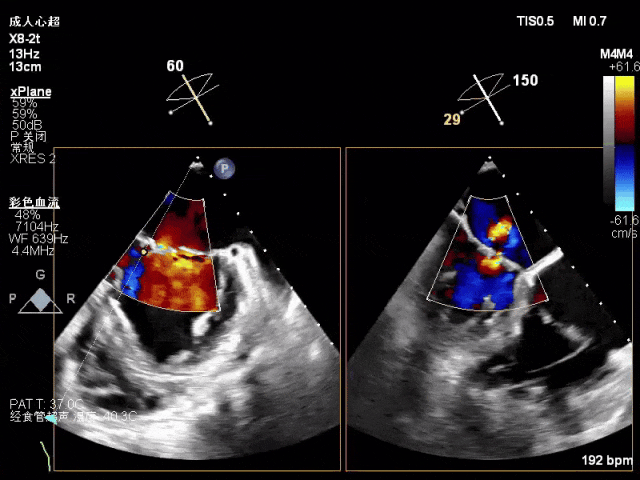

术中超声(关键步骤)

混合性MR,P2脱垂连枷(脱垂范围15mm,连枷间距4mm),腱索断裂

新分型:ACA型,反流2区及两侧,MR 4+,VC:3×14mm

A2:24mm,P2:17mm,AP:38mm,MVA约5.7cm²